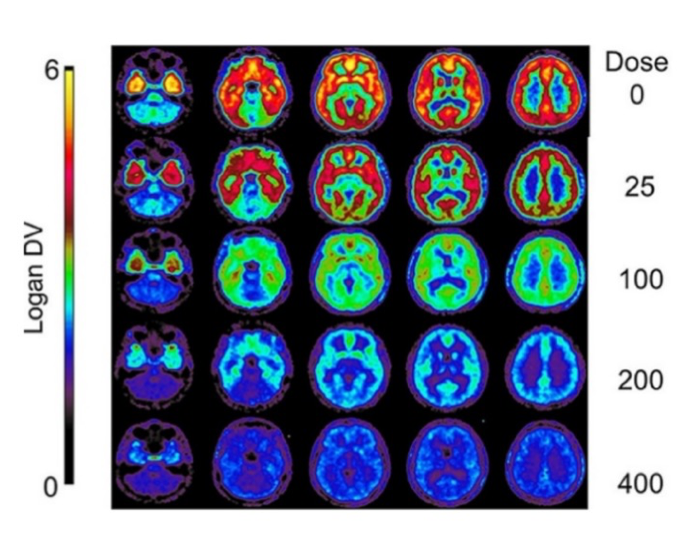

pmod’s tools provide comprehensive workflows for post-processing and quantification of imaging data for fundamental oncology research, development of radiotracers and theranostics, and in clinical research studies. Imaging scientists can trust pmod to reproducibly read their data, interpret the meta-data/units and help users calculate statistics such as SUV for their studies and publications.

For treatment evaluation and theranostic development

• Multimodality segmentation tools – comprehensive semi-automated and manual tools for precision and reproducibility

• Full access to metadata – ensure accurate calculation of Standard Uptake Value and other key statistics

• Flexible switching between 3D and 4D datasets – direct output of time activity curves